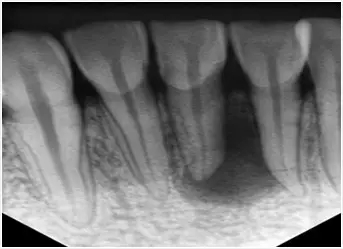

需要根管治療的牙片

中間黑色的是牙齒壞掉的部分